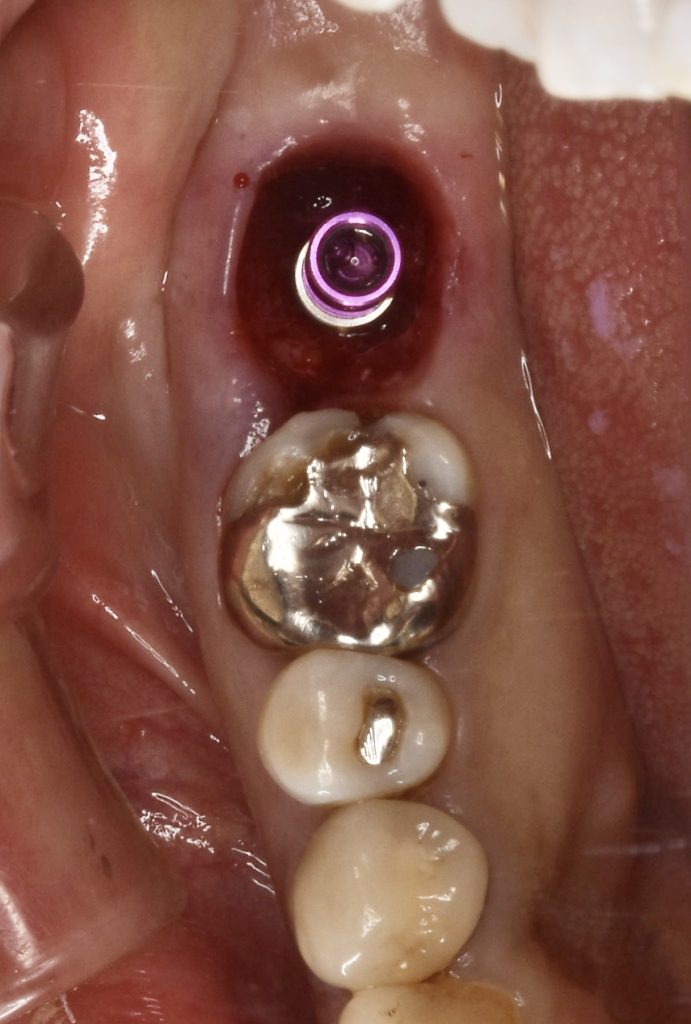

今回、古いメタルインレーの中でカリエスが進行し、骨縁下まで進行していました。

抜歯と同時にインプラント埋入手術を行い、4ヶ月ほどで治療を完了いたしました。